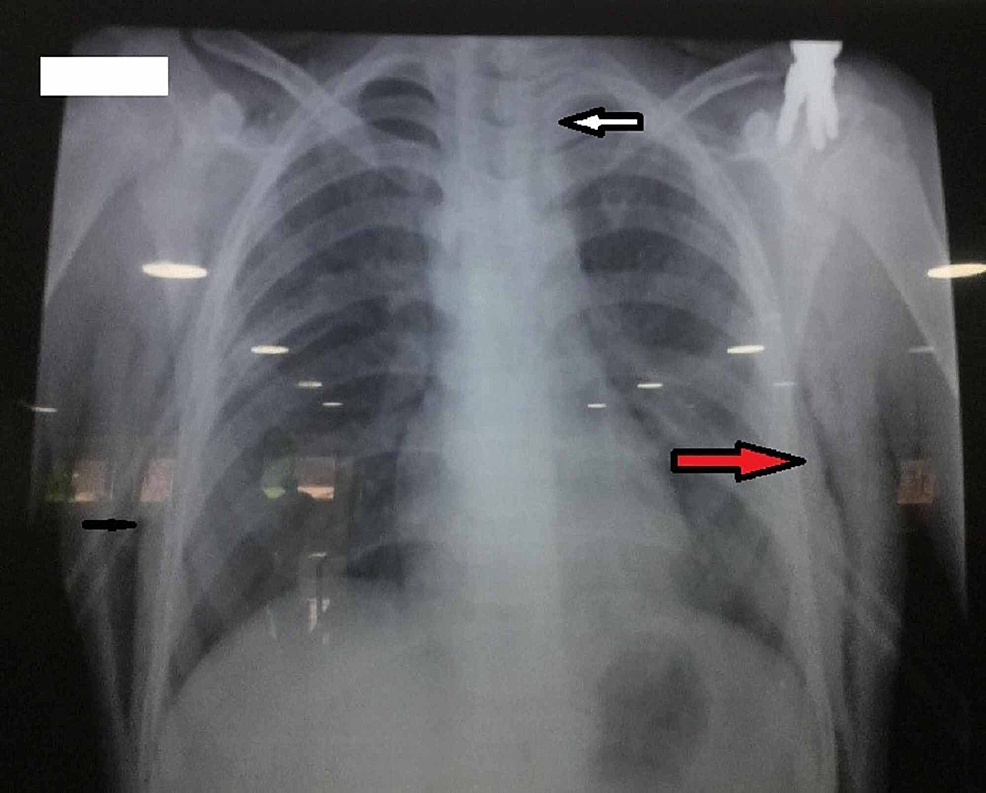

The chest X-ray was done, which showed lucent streaks of gas that outlined mediastinal structures (Figure 2).

The classical presentation is usually in patients with a history of varying degrees of shortness of breath, chest pain, difficulty swallowing, and subcutaneous emphysema (crepitation on touch), but our patient came to us with dyspnea. Physical examination of about 30% of patients can be normal in pneumomediastinum [3]. Usually, there may be tachycardia, tachypnea, hyper resonance to percussion, diminished breath sounds, and asymmetrical chest wall expansion may be present on physical examination. Distended neck veins, hypotension or cyanosis, and swelling on the chest radiate to the neck and face mostly due to underlying tension pneumothorax [4]. As in the presented case, the patient is hypotensive, tachycardiac, decreased breath sounds on the right side of the chest initially, and swelling on the chest and neck. However, diagnosis depends on the history and physical examination of the patient but can be confirmed by X-ray, CT of the chest, bronchoscopy for tracheal injuries, esophagoscopy for esophageal lacerations [6]. To make a correct diagnosis, frontal and lateral views of chest radiographs are needed. Accurate interpretation of the chest radiograph is essential in the early diagnosis of the occult upper-airway injury. Radiographic signs of pneumomediastinum on the X-ray of the chest include lucent streaks of gas that outlines mediastinal structures. The reported case was confirmed by X-ray and high-resolution tomography (HRCT) of the chest. Although bronchoscopy and esophagoscopy should be done to rule out any aerodigestive tract injuries, we did not perform it after consultation with a pulmonologist and gastroenterologist due to improvement in patient condition [7]. This is the major limitation in this case report. Whenever bilateral pneumothorax is suspected with pneumomediastinum, initial multidisciplinary evaluation is important for management. Bilateral pneumothorax can be treated according to age, clinical status, and underlying causes. It is usually benign in young patients and can be life-threatening in advanced ages and in patients with limited pulmonary reserve, requiring urgent management. Missed diagnosis and delayed treatment can lead to tension pneumothorax and the patient’s death [8, 9]. Aerodigestive tract injuries can be managed conservatively or by surgery, depending on patients' clinical status [3, 7]. Surgery is recommended for clinically unstable patients, as most patients with major aerodigestive tract injuries undergo primary repair. Pneumonia and mediastinitis prophylaxis should be given to all patients. Our patient became stable with bilateral chest tube thoracotomy and antibiotic cover, and the vitally stable patient was discharged after 10 days.